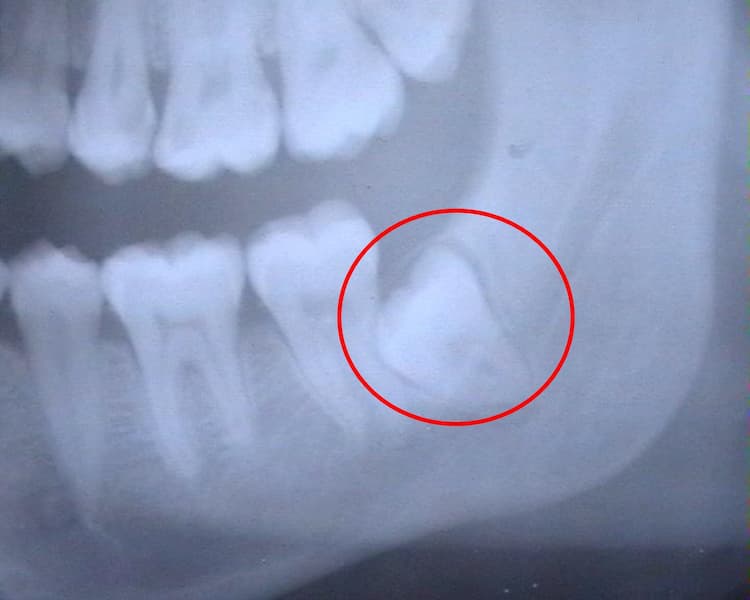

Weisheitszähne entfernen? Auf den Einzelfall kommt es an Nach spätestens einer Woche sind diese Reizungen allerdings komplett zurückgegangen und die Beschwerden verschwunden Die Dauer der ziehenden Schmerzen nach einer Weisheitszahn-OP kann von Person zu Person unterschiedlich sein In dieser Phase kann ein stärkerer Aufprall zu einem Bruch des Kiefers führen

Weisheitszahn OP! Schmerzen, Angst & Tipps Erfahrungsbericht YouTube . Schmerzen habe ich zwar noch etwas, aber ich denke das ist eine Woche nach der Operation noch völlig normal Durch die Entfernung der Weisheitszähne kommt es vorübergehend zu einer Schwächung des Unterkiefers